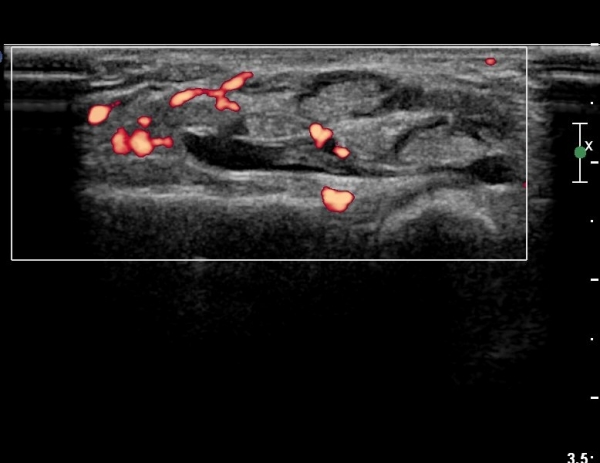

µµÇ÷¯°Ë»ç¿¡¼­ Ç÷·ùÁõ°¡°¡ °üÂûµÈ´Ù(»çÁø 2).